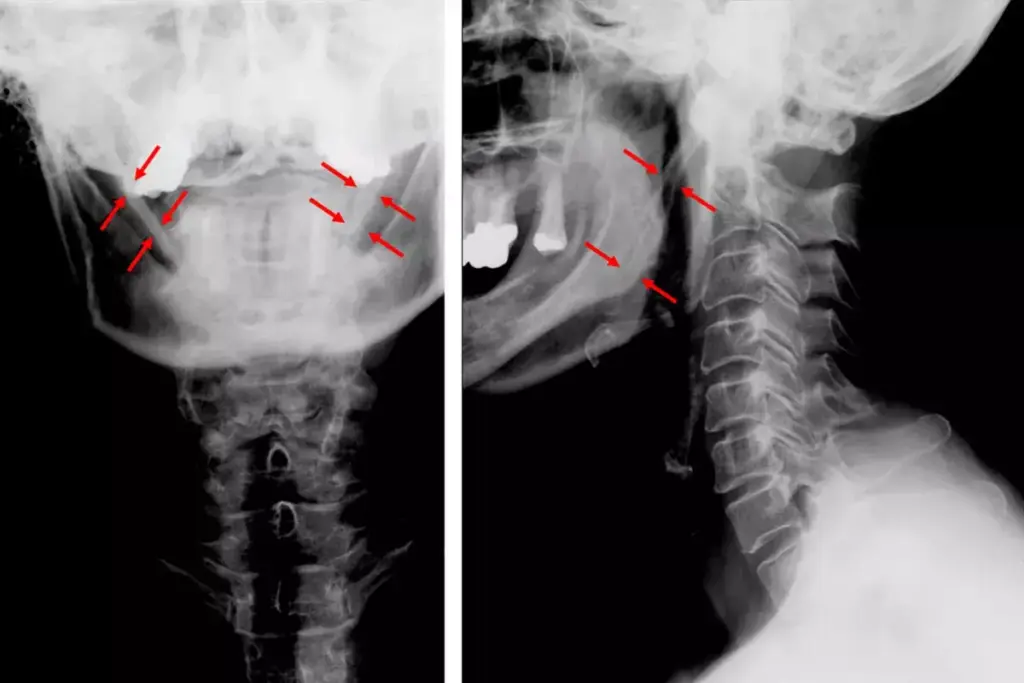

Key Anteroposterior (AP) Chest Findings

AP chest findings are key to understanding heart failure. They help doctors diagnose and see how severe it is. These findings are vital for diagnosing heart failure.

How do anteroposterior (AP) chest findings help in diagnosing heart failure?

AP chest X-rays allow doctors to identify physical signs of fluid overload, such as an enlarged heart shadow or fluid in the lungs (pulmonary edema). These findings help confirm that the heart is struggling to pump efficiently, causing blood to back up into the respiratory system.